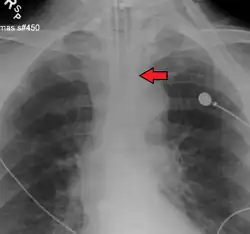

Idealmente, al menos uno de los métodos utilizados para confirmar la colocación del tubo traqueal será un instrumento de medición. La capnografía de forma de onda ha surgido como el estándar de oro para la confirmación de la colocación del tubo dentro de la tráquea. Otros métodos que dependen de instrumentos incluyen el uso de un detector colorimétrico de dióxido de carbono al final de la espiración, un bulbo esofágico autoinflable o un dispositivo de detección esofágica.[35] La punta distal de un tubo traqueal correctamente posicionado estará ubicada en la mitad de la tráquea, aproximadamente 2 cm (1 plg) por encima de la bifurcación de la carina; esto puede confirmarse mediante una radiografía de tórax. Si se inserta demasiado dentro de la tráquea (más allá de la carina), es probable que la punta del tubo traqueal esté dentro del bronquio principal derecho, una situación a menudo referida como "intubación del bronquio principal derecho". En esta situación, el pulmón izquierdo puede no participar en la ventilación, lo que puede llevar a una disminución del contenido de oxígeno debido a una desigualdad ventilación-perfusión.[36]

La punta de un tubo traqueal correctamente posicionado estará en la mitad de la tráquea, entre las clavículas en una radiografía de tórax anteroposterior. El diámetro correcto del tubo es aquel que resulta en una fuga pequeña a una presión de aproximadamente 25 cm de agua. El diámetro interno apropiado del tubo endotraqueal se estima como aproximadamente el mismo diámetro que el dedo meñique del niño. La longitud adecuada del tubo endotraqueal puede estimarse duplicando la distancia desde la comisura de la boca del niño hasta el canal auditivo. Para bebés prematuros, un diámetro interno de 2.5 mm es apropiado. Para bebés de edad gestacional a término, un diámetro interno de 3 mm es adecuado. Para niños de 1 año o más con nutrición normal, se utilizan dos fórmulas para estimar el diámetro interno y la profundidad de inserción del tubo: el diámetro interno en mm es (edad en años + 16) / 4, mientras que la profundidad de inserción en cm es 12 + (edad en años / 2).[33]